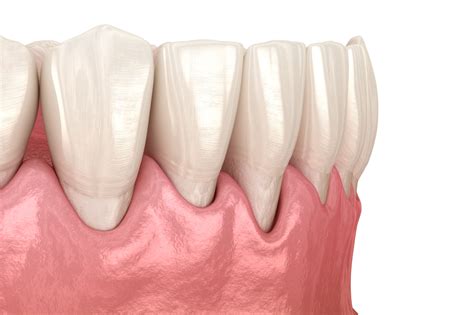

A flap in gums occurs when the gum tissue pulls away from the tooth, exposing the root. This can lead to various issues, including sensitivity, pain, and an increased risk of tooth decay. The condition can be caused by several factors, including poor oral hygiene, gum disease, and aggressive brushing.

• Visible Recession: The gum tissue appears to be pulling away from the tooth, exposing the root.

• Gum Grafting: In severe cases, a gum graft may be necessary to cover the exposed root and restore the gumline.

In severe cases, surgical intervention may be necessary to restore the gumline and cover the exposed root. Gum grafting is a common procedure used to treat gum recession. During the procedure, a small piece of gum tissue is taken from another part of the mouth and attached to the affected area. This helps to cover the exposed root and promote healing.